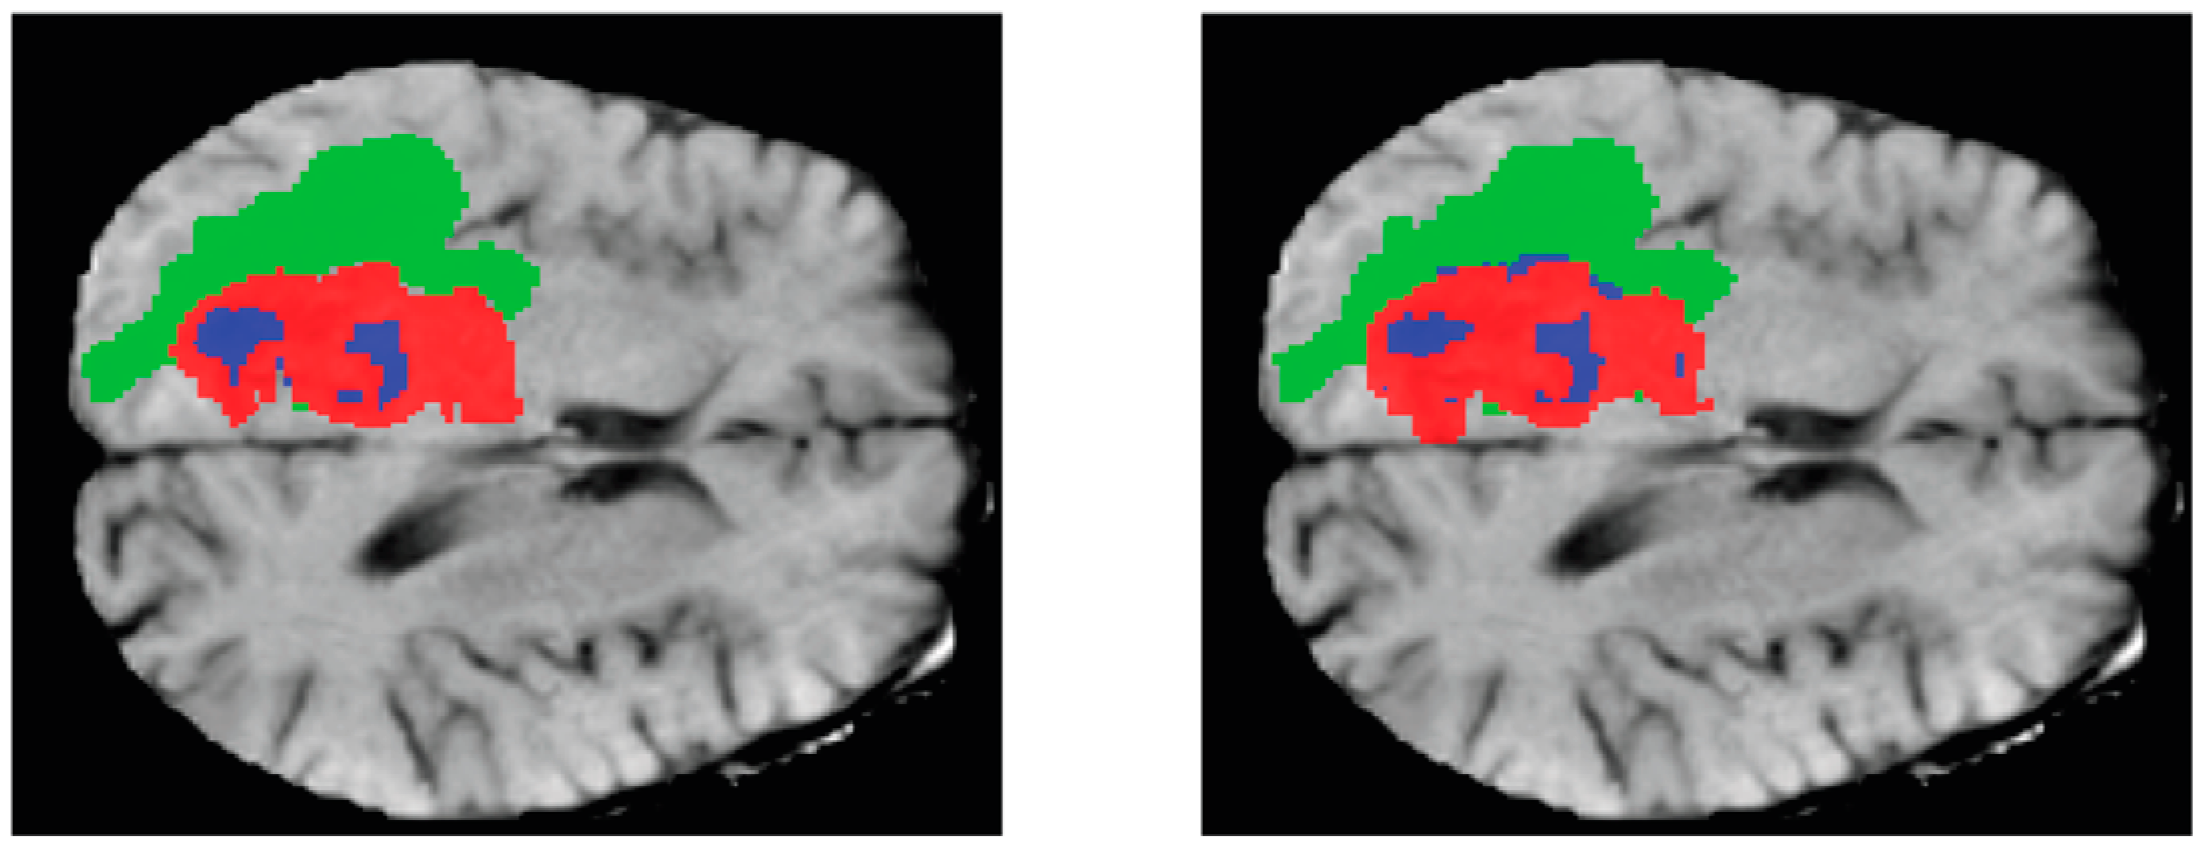

The approach used in this research involved the utilization of the brain tumor segmentation challenge dataset (BraTs 2021). The dataset was publicly released during the MICCAI conference and was subsequently utilized in a competitive setting, allowing the participating groups to evaluate their novel methodologies using this dataset. The BraTs 2021 dataset comprises three-dimensional magnetic resonance imaging scans of individuals. The Hold-Out strategy was employed to partition the dataset into two distinct subsets, namely the training set and the test set. The training set constituted 80% of the dataset, while the remaining 20% was allocated to the test set. Figure 6 shows the instances inside the dataset, along with a visual representation of their corresponding actual states in a three-dimensional space.

Figure 6.

Samples in the dataset.

The representation of three-dimensional (3D) images on paper is often challenging, thus necessitating the display of the two-dimensional (2D) parts of these images. Figure 7 is an instance from the dataset, whereby three cuts have been made along the three axes of the image. The leftmost column displays the Flair channel images of the sample. The middle column exhibits the equivalent slices extracted from the real-state image. Lastly, the rightmost column portrays the amalgamation of the two columns, revealing three distinct tumor locations on the brain image, each represented by a different color, having undergone a transformation. The provided photos depict the inflamed region of the tumor in a green hue, the necrotic tissue of the tumor in a blue hue, and the actively proliferating core of the tumor in a red hue.

Figure 7.

Images of tumor swelling area with three different colors.